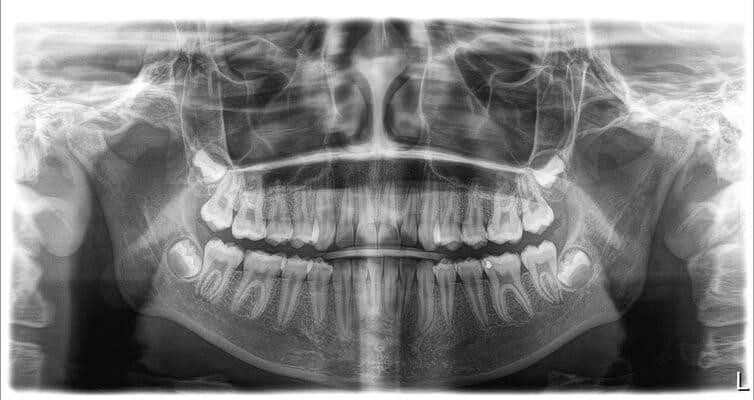

Дівчинка 7 років, перше вересня, гойдалка… Вивих постійного зуба: якщо в такій ситуації зволікати, дитина може втрати постійний зуб назавжди. Батькам порекомендували нас і пацієнти одразу приїхали. Через складність і травматичність процедур вирішено проводити лікування в анестезіологічному супроводі. Зуб поставлений на місце (репонований), проведена хірургічна обробка і ушивання рани губи. Останнє фото через рік після травми: зуб на місці і корінь продовжує розвиватись, губа повністю загоїлась